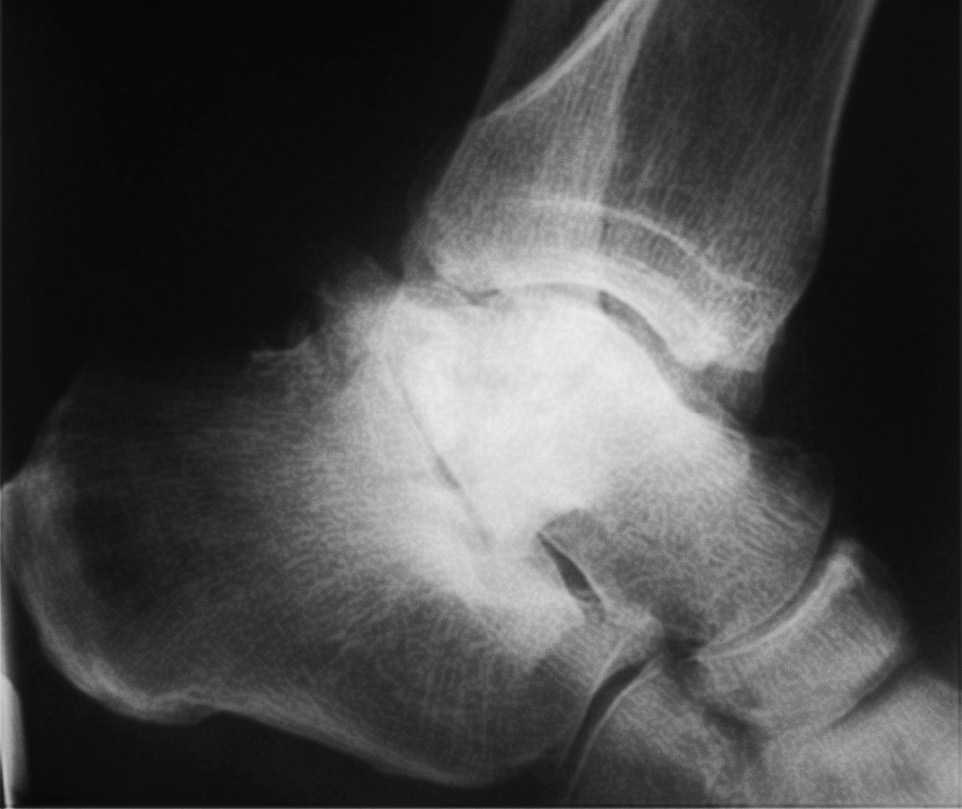

El seguimiento a la largo plazo de las fracturas del astrágalo identifica que la causa más común de los resultados pobres está asociada con la OA subastragalina, tibioastragalina y talonavicular, tanto en nuestra revisión, que alcanzó al 21% (8) de los casos (figs. 9 y 10), como en otros trabajos revisados15,17,19,22,23.

Fig. 9. --A) Fractura del cuerpo del astrágalo tipo B más rotura completa de los 3 ligamentos laterales del tobillo. B) Abordaje bilateral. Osteosíntesis. Sutura de ligamentos. Radiografía y tomografía computarizada a los 18 meses. Artrosis subastragalina y tibioastragalina.

Fig. 9. --a: Type B fracture of the astragalus with complete rupture of the 3 lateral ankle ligaments. b: Bilateral approach. Osteosynthesis. Ligament suture. Radiography and CT at 18 months. Sub-astragalar and tibio-astragalar arthrosis.

Fig.10. --Resultado a los 32 meses. 50° de BA. NAV del cuerpo y artrosis subastragalina y tibioastragalina

Fig.10. --Results at 32 months. BA 50º. Avascular necrosis of the astragalus and sub-astragalar and tibio-astragalar arthrosis.